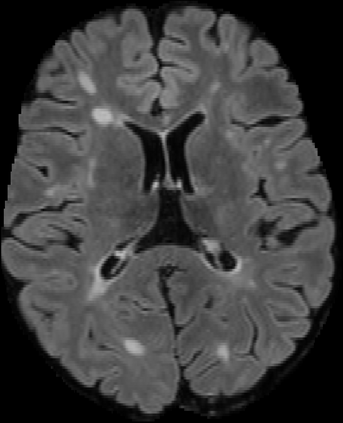

Assessment of lesions and their longitudinal progression from brain magnetic resonance (MR) images plays a crucial role in diagnosing and monitoring multiple sclerosis (MS). Machine learning models have demonstrated a great potential for automated MS lesion segmentation. Training such models typically requires large-scale high-quality datasets that are consistently annotated. However, MS imaging datasets are often small, segregated across multiple sites, with different formats (cross-sectional or longitudinal), and diverse annotation styles. This poses a significant challenge to train a unified MS lesion segmentation model. To tackle this challenge, we present SegHeD, a novel multi-dataset multi-task segmentation model that can incorporate heterogeneous data as input and perform all-lesion, new-lesion, as well as vanishing-lesion segmentation. Furthermore, we account for domain knowledge about MS lesions, incorporating longitudinal, spatial, and volumetric constraints into the segmentation model. SegHeD is assessed on five MS datasets and achieves a high performance in all, new, and vanishing-lesion segmentation, outperforming several state-of-the-art methods in this field.